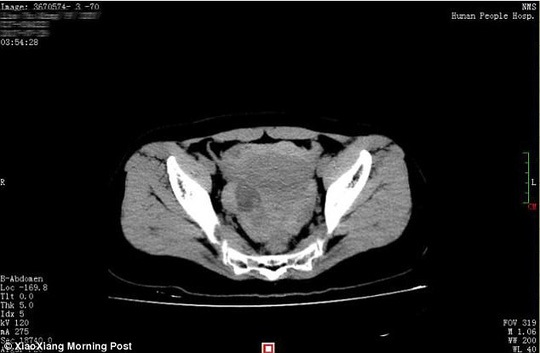

Hình ảnh scan của Xiao Qing cho thấy xuất huyết máu ồ ạt trong vùng khoang xương chậu. Ảnh: Xiaoxiang Morning Post.

Vết thương từ nang buồng trứng khiến người vợ trẻ mất gần 40% lượng máu nhưng may mắn cô vẫn sống sót.

Theo lời bác sĩ Huang Mei tại bệnh viện Hunan, cô Xiao Qing không có bầu nhưng bị mất một lượng máu lớn ở phần ổ bụng và khung xương chậu.

"Có khoảng 1.500ml máu bị mất từ phần bụng của bệnh nhân, chiếm khoảng 40% lượng máu của cô. Nếu tới bệnh viện trễ hơn, tính mạng của bệnh nhân có thể đã bị đe dọa" - bác sĩ Huang Mei nhấn mạnh.

Các bác sĩ cũng tìm thấy một nang buồng trứng bị vỡ bên buồng trứng bên phải của Xiao Qing. Nang buồng trứng vốn là một túi dịch thường không phải là ung thư.

Bệnh nhân sau đó đã được phẫu thuật để bỏ nang bị vỡ đó đi để chữa trị buồng trứng bị tổn thương.